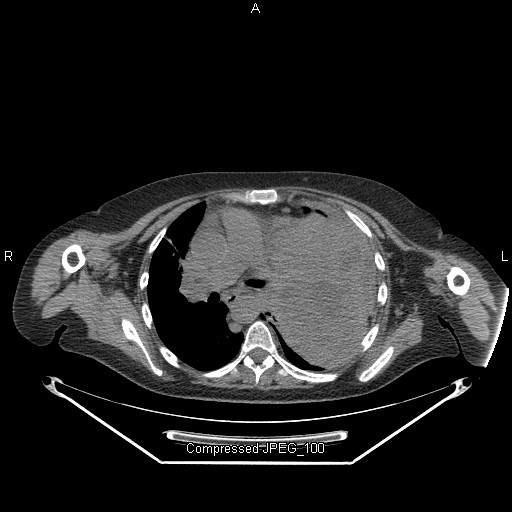

The extent of blunt aortic injuries vary from false aneurysm, and per aortic hemorrhage. Interestingly, this classification proves that this injury starts in the inside The theory neatly provides an explanation as to why thoracic aortic disruption nearly always occurs in the same place ... Return Doc

Blunt thoracic aortic injury 2. Grossly positive DPL 3. Classification • Those who reached the hospital alive have partial disruption of the intima and medial only – Grade I to III Endovascular-Techniques-Tran Author: shellym1 ... Access This Document